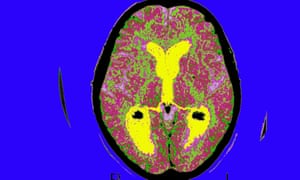

Humans can make new brain cells into their 90s, scientists discover

Humans can make fresh brain cells until they are well into their 90s, but the production of new neurons falls in those with Alzheimer’s, even when the disease has recently taken hold, scientists have found.

The new cells were born in the part of the brain called the dentate gyrus. It is a part of the hippocampus which plays a central role in learning, memory, mood and emotion. The gradual reduction in new brain cells appeared to go hand-in-hand with the cognitive decline that comes with old age. It suggests that in middle age about 300 fewer neurons per cubic millimetre are made in the dentate gyrus with each advancing year.

Having studied healthy brain tissue, the scientists went on to look at the brains of people who had been diagnosed with Alzheimer’s before death. This time, the researchers analysed brain tissue from 45 patients aged 52 to 97. All had fresh brain cells in the dentate gyrus, including the 97-year old, the oldest person in which “neurogenesis” has yet been seen.